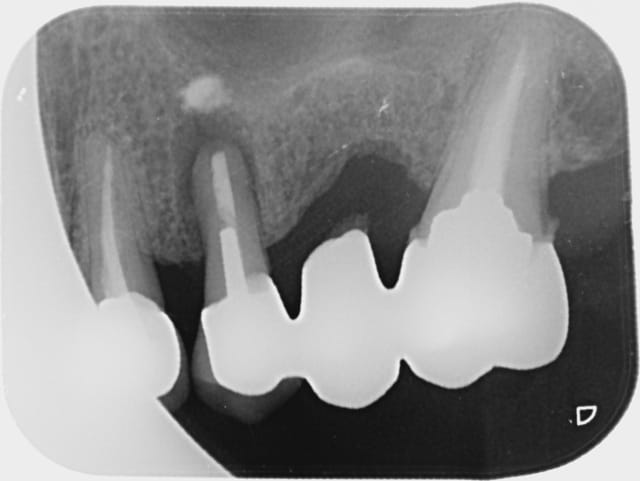

Je balance entre vous fournir une radio sans commentaire ou la vengeance est un plat qui se mange froid...

Patient vu en octobre 2009 , fidèle depuis années 80 . Il faut remplacer la 26 , proposition ostéotension , implant , devis . La 25 ne me branche pas pour un bridge .

Mai 2010 , pb paro léger en mésial de la 27 . Surprise : Oh , un bridge ?

Mais qu'est ce que d'où est ce qu'il vient-il me dis-je en me le disant à moi même en me le disant que je lui avais dit à l'époque que les prémos du haut...ouin . Le patient habite depuis à 15 kms , je ne dis rien .

Ce matin abcès sur la 25 ...